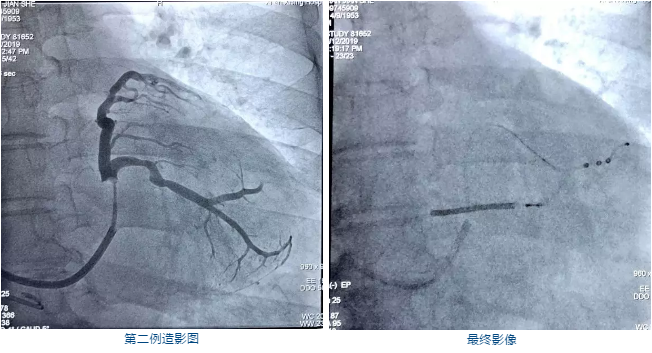

本次两例患者均为CRT治疗的经典适应证,心电图提示:LBBB,QRS>150ms,心脏超声提示:EF<35%,全心大。根据2016年ESC心衰指南,为CRT植入的Ia类适应证。

这两例案例造影后特点鲜明,靶血管侧静脉主支粗大,并延伸至心尖,两位教授选用了ACUITY Spiral S 以保证螺旋更好贴靠血管。导线进入主支后,有膈神经刺激,重新进入分支后,阈值参数良好并固定牢靠,整个过程中Spiral S导线表现了良好的通过性。